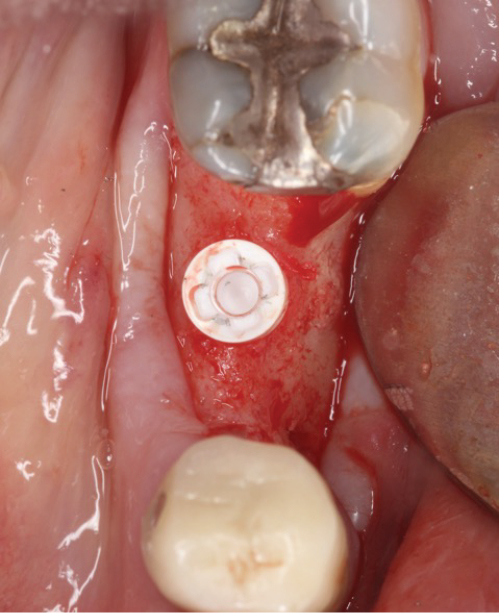

Peri-implant mucositis can be defined as an inflammatory lesion of the soft tissues (mucosa) surrounding the dental implant. Peri-implantitis is an inflammatory lesion of the mucosa affecting the supporting bone (crestal bone) with crestal bone loss and loss of osseointegration. Derks et al. report a prevalence of 43% for peri-implant mucositis and Jepsen et al. estimate that the prevalence of peri-implantitis could reach 22% (Figs. 1, 2).2,3 Peri-implantitis is usually accompanied by crestal bone loss (Fig. 3) and soft tissue changes in the peri-implant sulcus, which can be diagnosed by an increase in bleeding on probing (BOP) more than 5mm over previous examinations and/or suppuration8 (Fig. 4). Also excess of residual cement might contribute to crestal bone loss (Fig. 5).7

Recently, ceramic implants were introduced as alternative strategy with the aim of preventing the development of peri-implantitis and bone loss (Fig. 6). Compared to titanium implants, studies show that zirconia implants are associated with lower plaque and bleeding scores.15-17 Ceramic implants offer high resistance to corrosion, better peri-implant soft tissue conditions and less inflammation as well as lower oral biofilm adhesion. Apart from the excellent mid-term clinical outcomes, such as a high cumulative survival rate and a low level of average crestal bone loss, zirconia implants contribute to the aesthetics of dental restoration. The white color of zirconia comes close to that of natural teeth.15,18 If the long-term clinical results of ceramic implants are confirmed to be equal to or better than the metal alternative, there is potential for a general switch to ceramics in the future.

Based on current evidence and studies suggesting that zirconia dental implants are associated with less peri-implant inflammatory reactions and less crestal bone loss (Fig. 7), we decided to investigate the behavior, the mechanical stability and the clinical outcomes of ceramic implants at our institution. The first patient implantations look promising. But long-term studies will be required to develop strong evidence and convince the large majority of dental implant surgeons to use zirconia dental implants as routinely as orthopedic surgeons do in hip replacement.